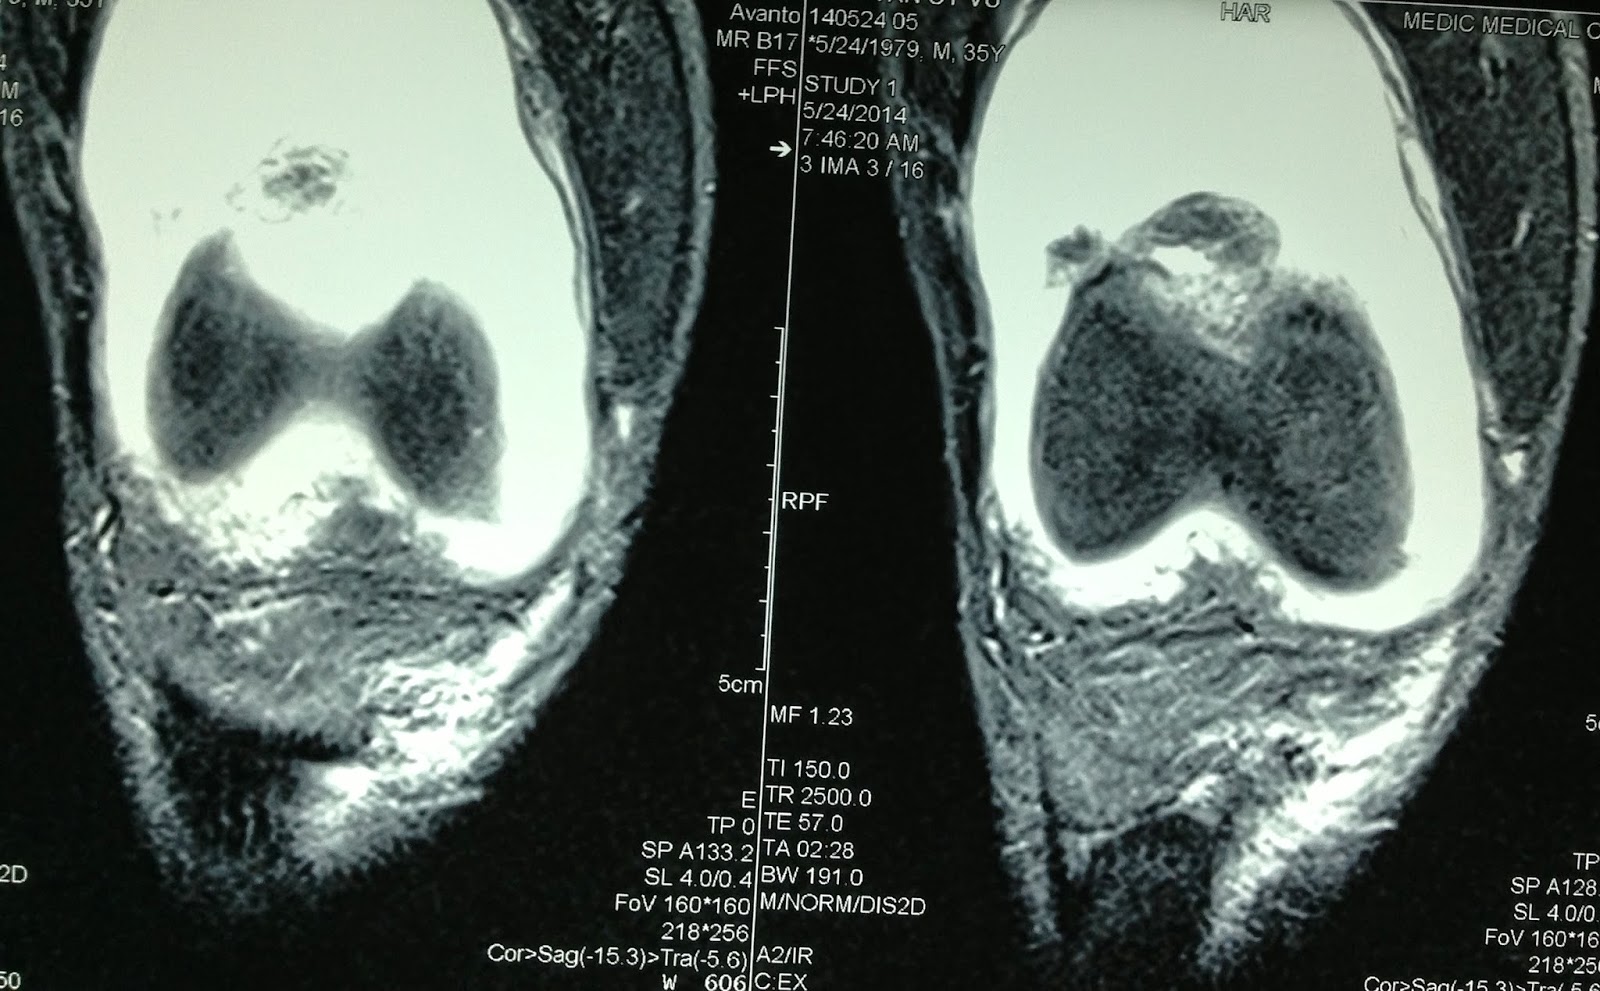

Man 35 yo, 3 days ago, pain at right knee cannot move, fever, no history of trauma. Clinical examination of right knee: hot and swelling at suprapatellar area (see photo).

Ultrasound first scanned at the right knee, detecting swelling of the suprapatella recessus with homogeneous fluid (2 ultrasound pictures).

Diagnosis of this case is acute bacteria infection of the knee joint, emergency treated with antibotic and analgesic drugs.